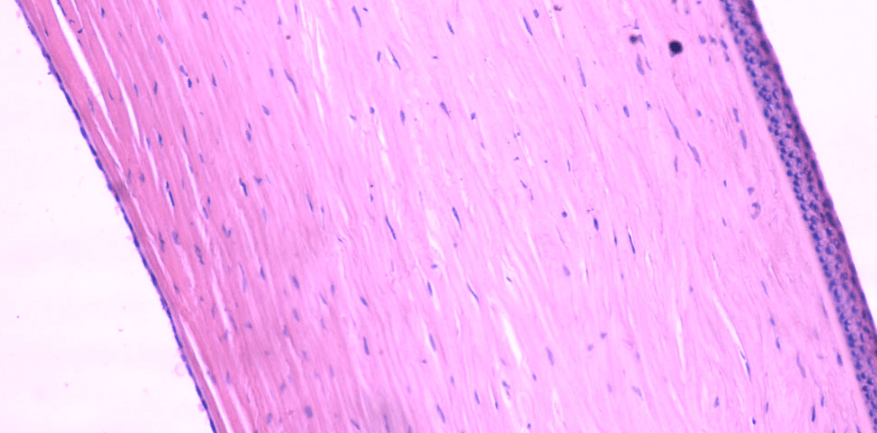

CÓRNEA

Consta de 5 capas:

1. Epitelio corneal

2. Membrana de Bowman

3. Estroma corneal

4. Membrana de Descemet

5. Endotelio corneal